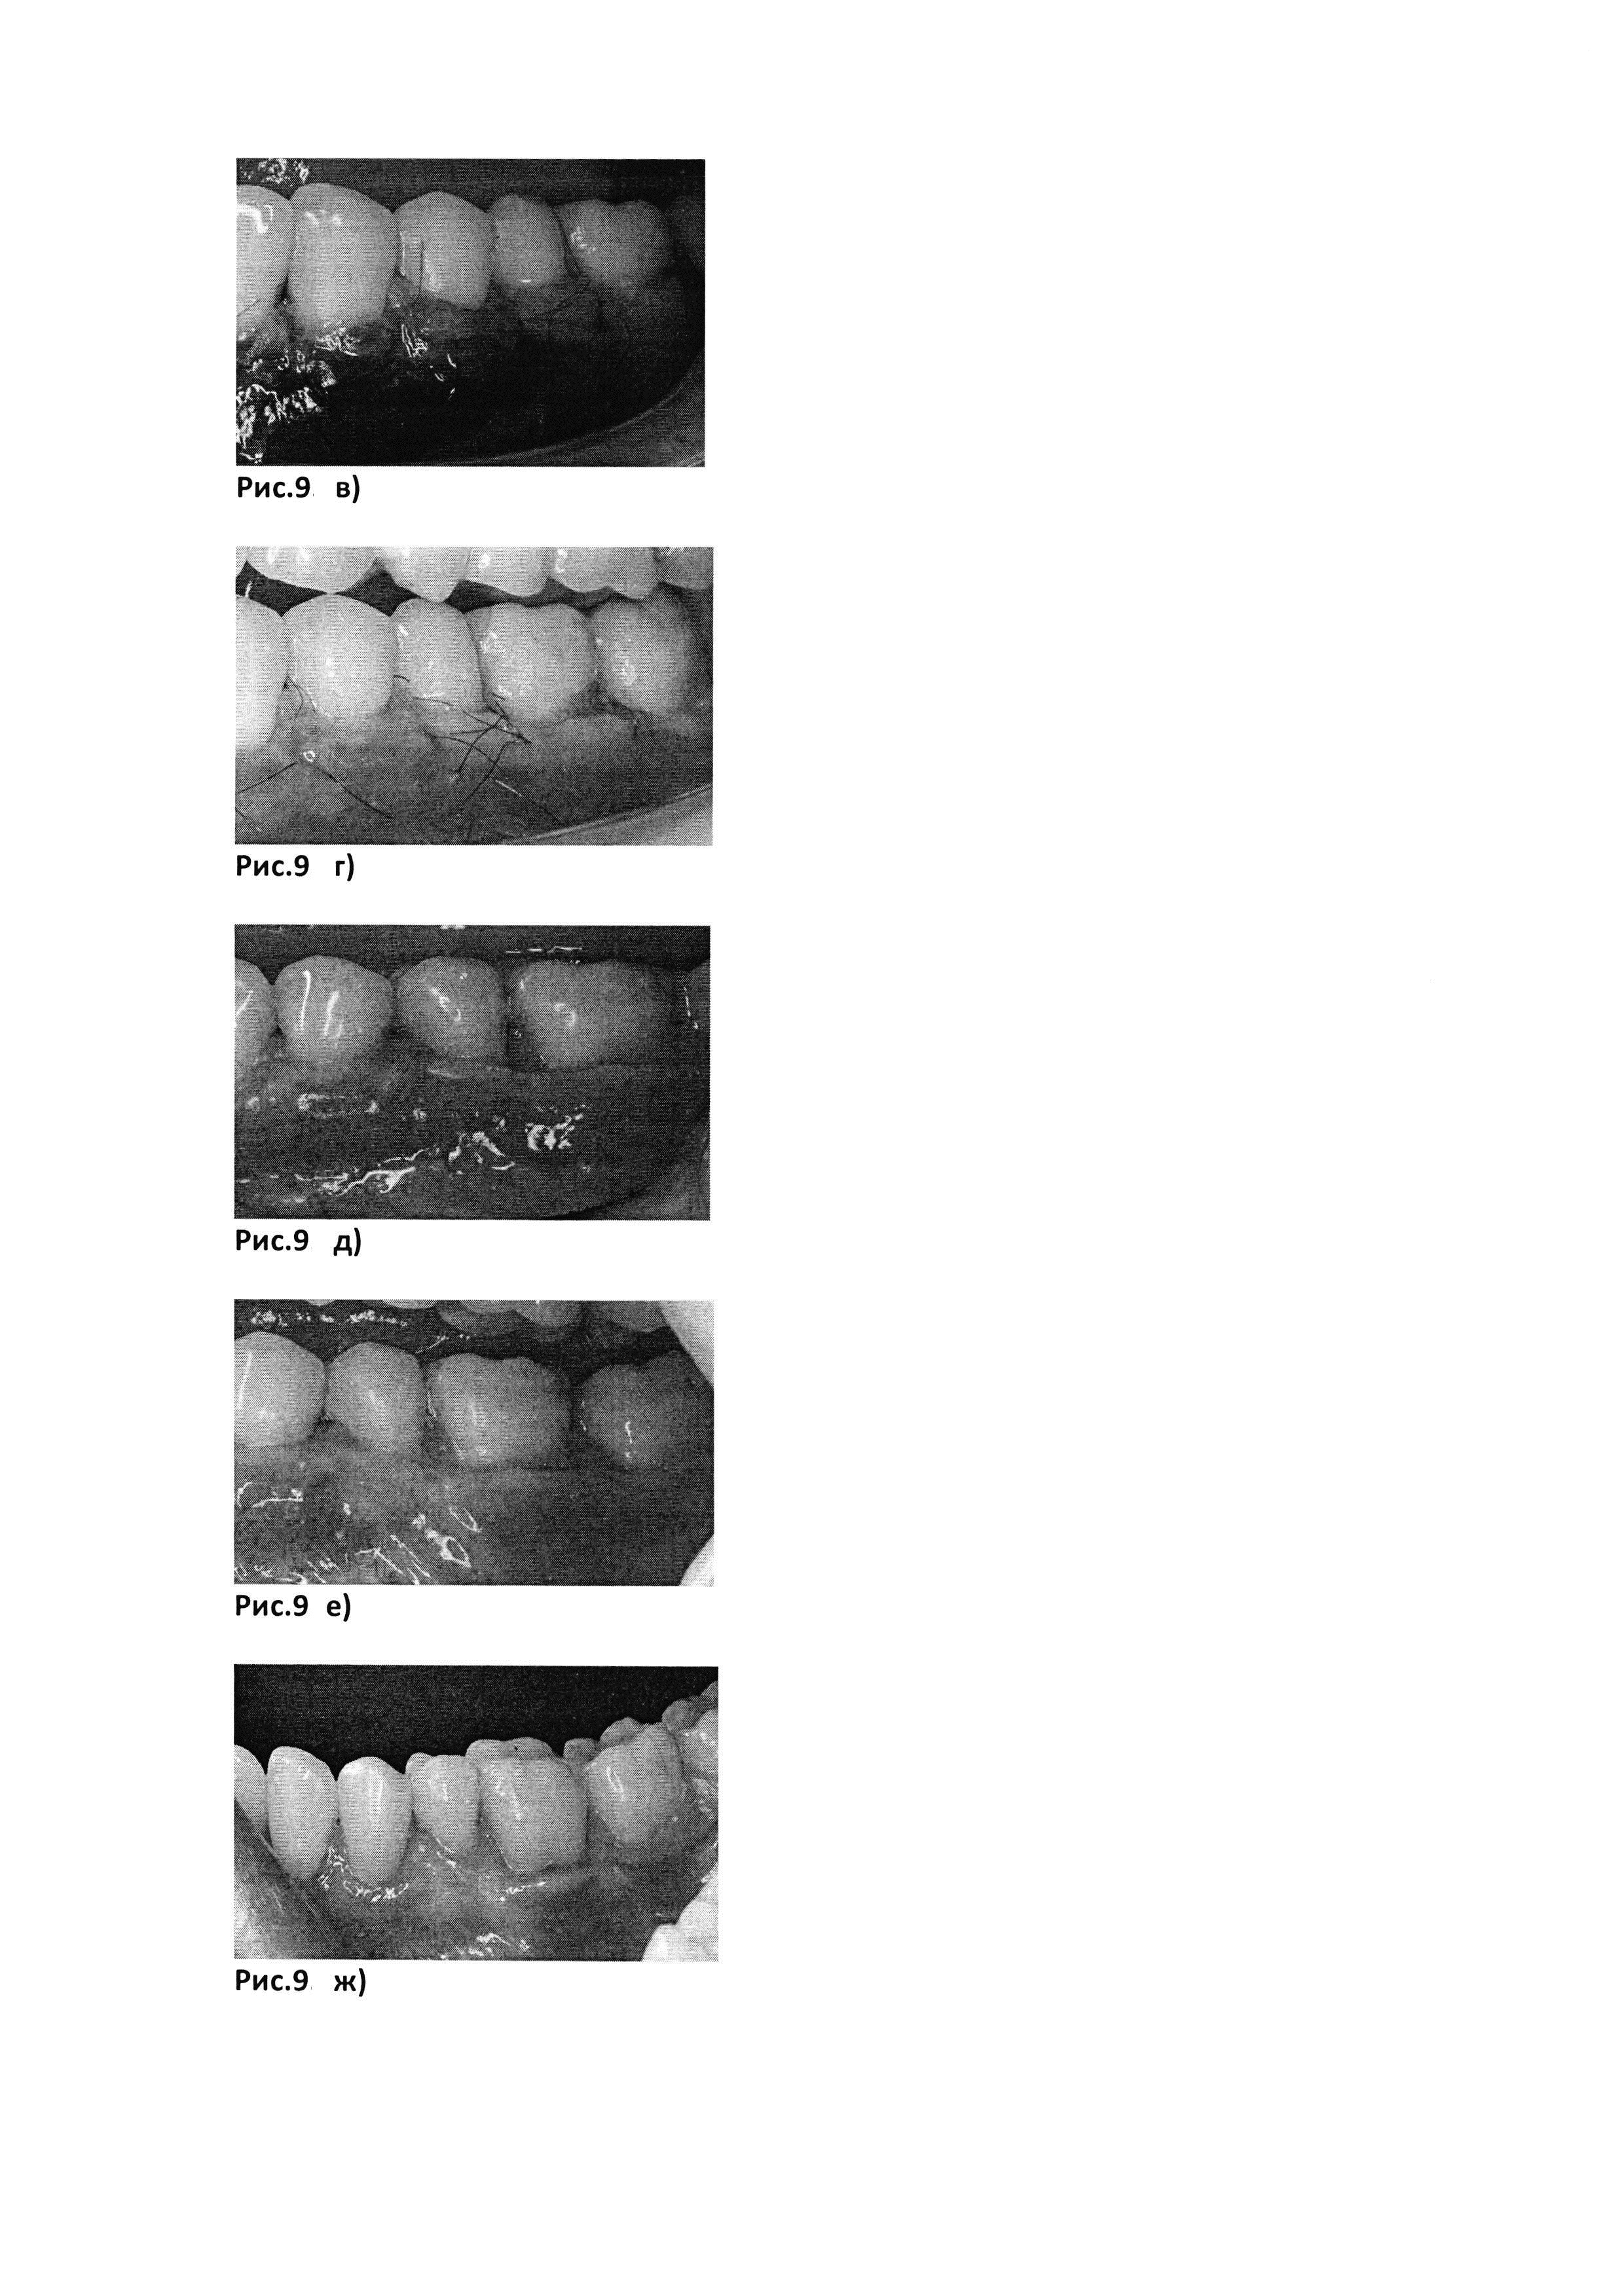

Рис. 9. Клинический пример №2.

[40]

Рис. 9, б) Биотрансплантат, представляющий собой PRF-мембрану (полученную с помощью центрифуги Scilogex, USA (РУ №РЗН 2015/3442) с интегрированными в нее аутоФС пациентки.

[41]

Рис. 9. а) до лечения

[42]

Рис. 9. в) сразу после операции

[43]

Рис. 9. г) через 12 дней после операции

[44]

Рис. 9. д) через месяц после операции